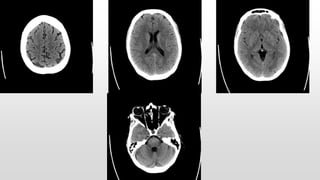

This document discusses various cases of collapse and syncope. It defines collapse as transient loss of consciousness with loss of postural tone and full recovery. Syncope is defined as loss of postural tone with or without loss of consciousness and full recovery. It then discusses the multiple potential causes of collapse and syncope including toxicological, cardiac conduction abnormalities, structural cardiac issues, autonomic dysfunction and more. It then goes through 9 case examples, discussing important questions to ask, potential tests and interventions for each case.